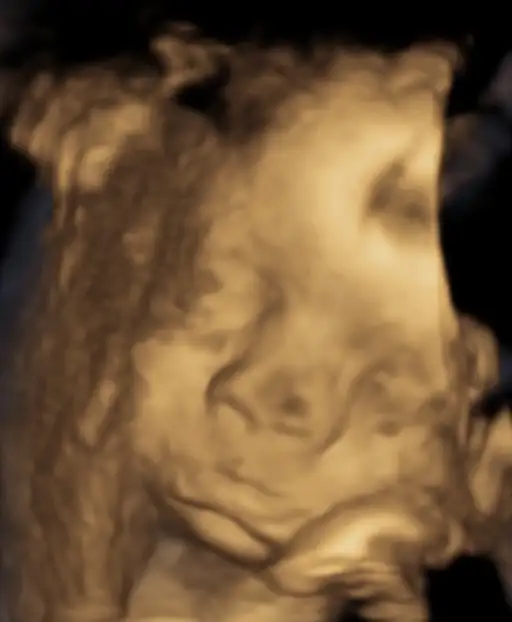

1230 gr37 cm olmuş güzel kızım

Herşey yolunda rahim ağzı kapalı serviks uzunlugu 43 dedi. Yüzünü plasentaya dayamış yine sağolsun pek net resim alamadık